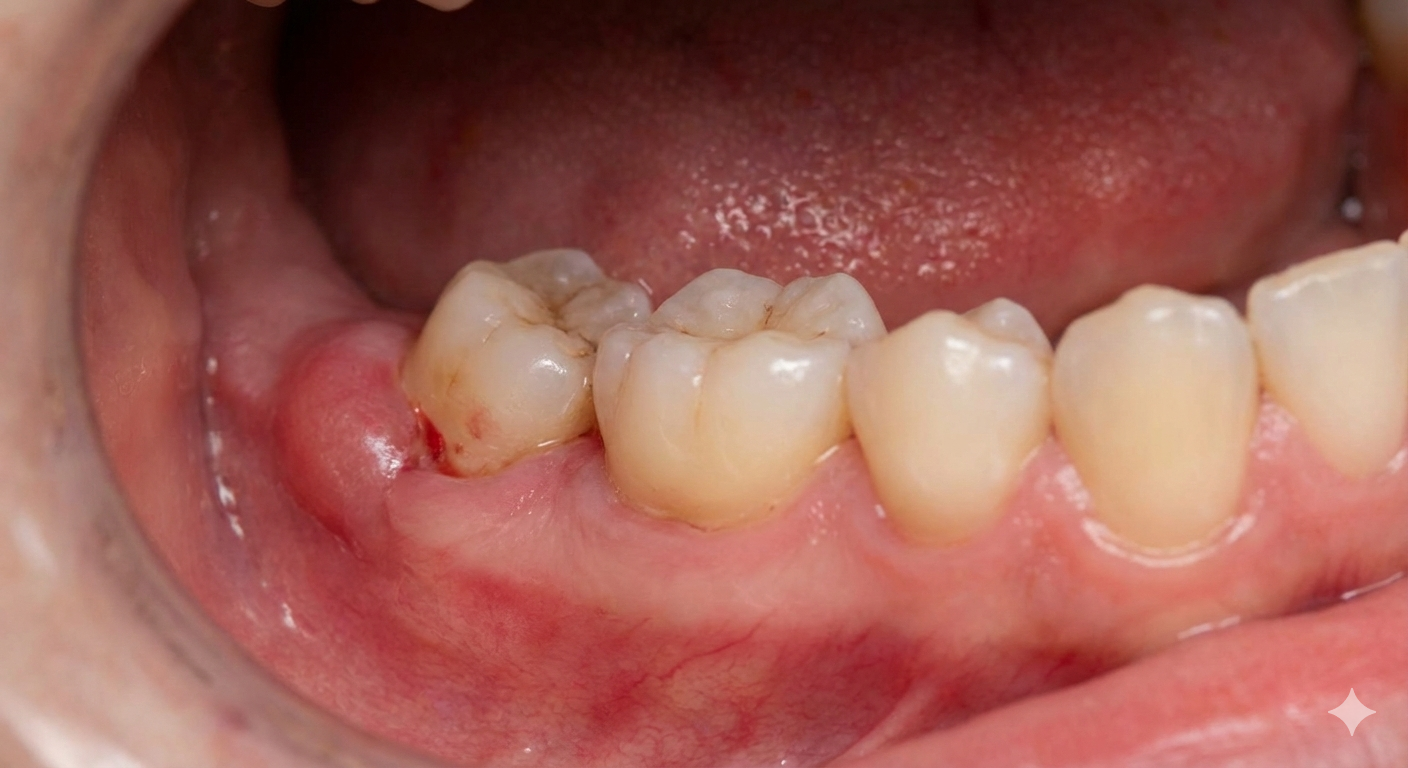

Certain dental issues require surgical intervention, and minor oral surgery provides targeted relief for a healthier, pain-free mouth.